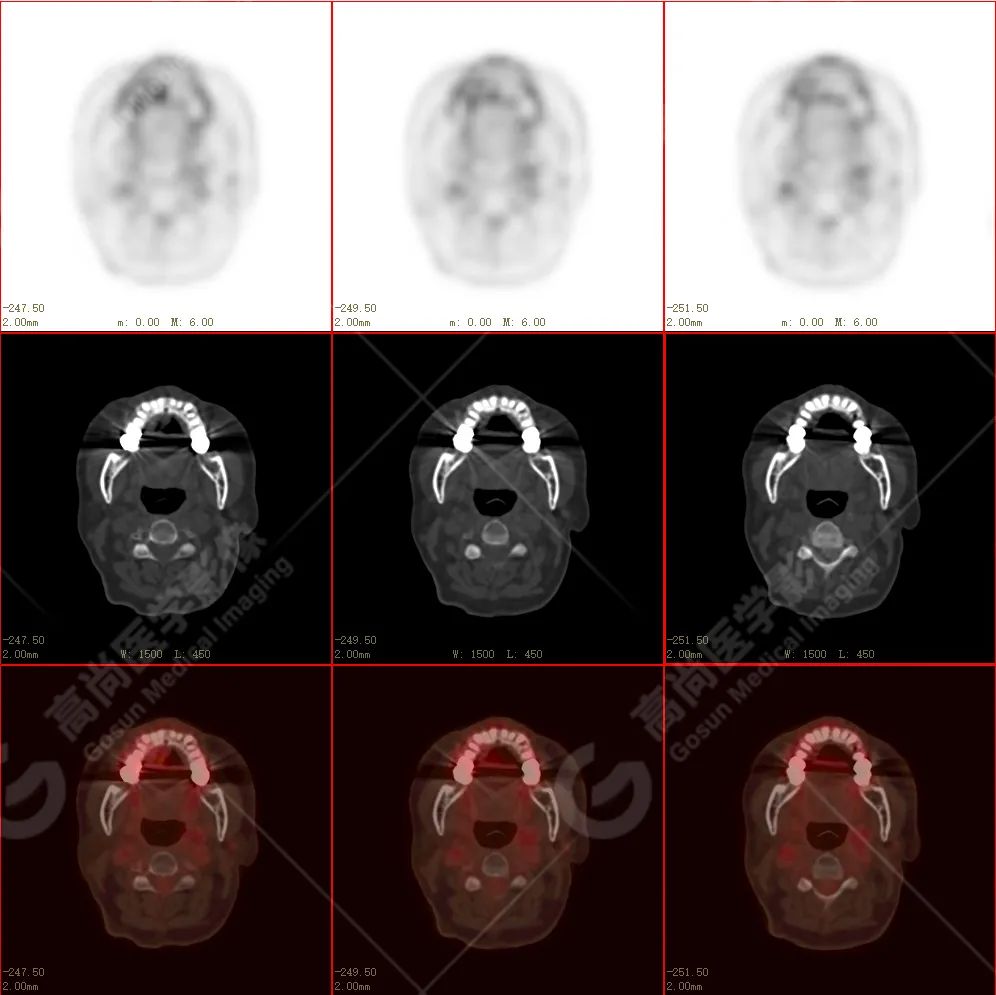

右侧上颌骨-上颌窦骨壁-骨性鼻中隔区域见片块状放射性摄取异常增高影,最大层面约 4.1 cm×3.8 cm×2.8 cm,SUV 最大值为 10.4,CT 示上述部位见成骨性改变,骨质不均匀弥漫性增厚、密度不均匀增高,并可见肿瘤骨影,边缘毛糙,周围伴软组织增厚。